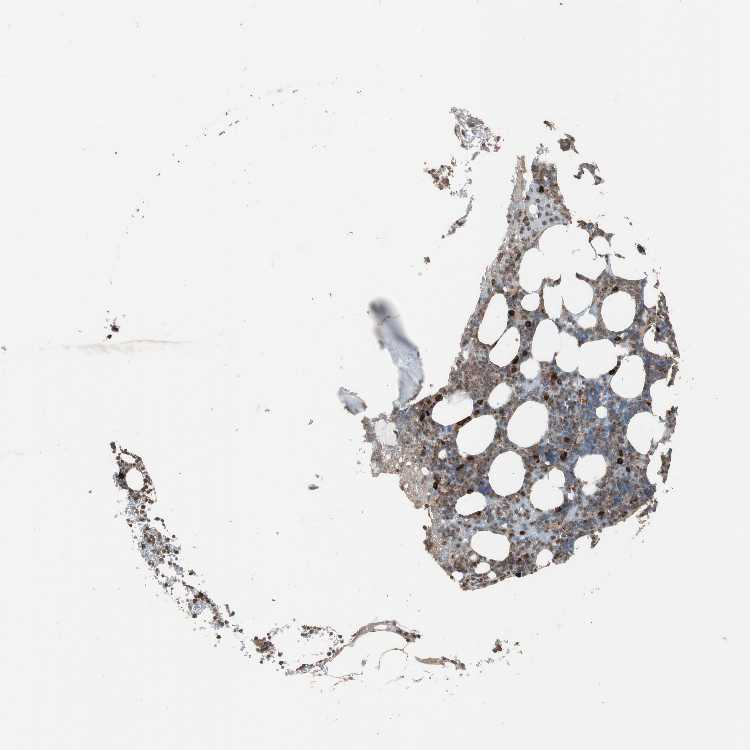

LZTS1